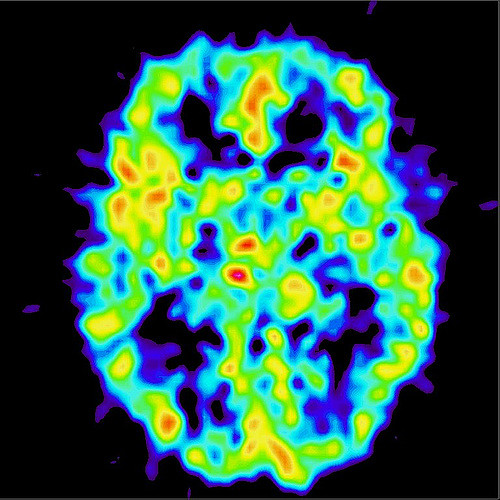

It wasn’t until the development of a technique called the PET scan (for Positron Emission Tomography) that we have been able to learn what is happening inside the brain — without damaging it. A person undergoing a PET scan will be injected with small amounts of a radioactive material — exactly what depends on the purpose of the scan. They are then imaged by a scanner to see where the tracer ends up, and this indicates the most metabolically active area with respect to that tracer. In the endorphin study that tracer was a chemical that specifically binds to opioid receptors* — in this case the endorphins’. The particular receptors targeted were the so-called -opioid receptors or MOR. So areas of the brain that are most active with endorphins will ‘light up’ and can be seen on the image.

In their study, Dr. Jetro J. Tuulari from the University of Turku, Finland, and colleagues studied the brain PET scans of 10 healthy men (20-35 years old) in three conditions: after a palatable meal, after a non-palatable meal, and after an overnight fast.

As expected, the pizza meals achieved a significantly more positive ‘tastiness’ rating than the nutrient drinks. But there were no differences between them with respect to the satiety levels participants reported. The PET scans revealed consumption of both meals caused widespread endogenous opioid release compared to the fasting state of each participant. Unexpectedly, there was more opioid release after the non-palatable meals than after the pizza; and there were more brain regions involved after the nutrient drinks as well. The differences between the non-palatable meals and fasting were highly statistically significant, while those between the palatable meals and fasting were only marginally significant.